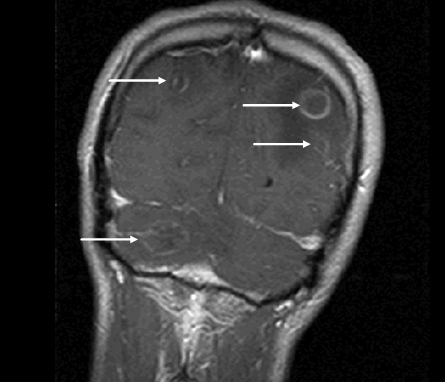

This patient with HIV has neurologic symptoms (headache, confusion, focal deficits), fever, and evidence of ring-enhancing lesions on MRI, strongly suggesting toxoplasmosis.